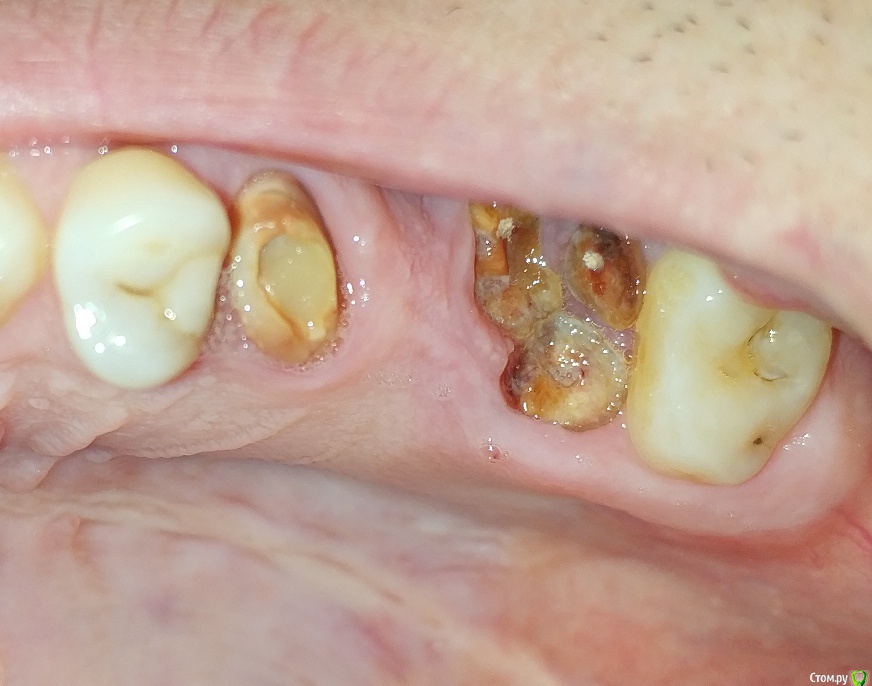

LTD Опубликовано 12 апреля, 2019 Поделиться Опубликовано 12 апреля, 2019 Мужчинка, 45 годов Слетел верхний мост 5-7 . Корень 7 (основание зуба ) отделился / разделился. «Целые» зубы 4, 8 не хочу трогать (обтачивать), решение зависит от бюджета. Просьба высказать мнение :а) Без имплантологии1 - делается ли вкладка на 7ку под дальнейший мост в таком состоянии? 2 - какие варианты восстановления возможны (съемные, бюгель и тд)?3 - какие варианты восстановления наиболее практичны по Вашему? б) хотя имплантация пока не по зубам Хочу понять:3 - на противоположной стороне 7-8 удачно стоит МК консоль на одном 7 зубе. Делается ли имплант с такой же конструкцией консоли на один 7-мой (который разрушен)?4 - делается ли одноэтапная имплантация на 7?5 - имеет ли смысл не удалять корни 7го с этой целью?6 - если 7 имплант + 567 мост (ставится ли мост - конструкция на 5й "свой") ?7 - возможность установки 7 без открытого лифта? Заранее спасибо! Ссылка на комментарий

krokomot Опубликовано 13 апреля, 2019 Поделиться Опубликовано 13 апреля, 2019 Вот могут же пациенты, себя хорошо сфотографировать, что всё видно и понятно, присоединяюсь к коллегам, но нижний зуб под коронкой тоже от жил свое... 2 Ссылка на комментарий